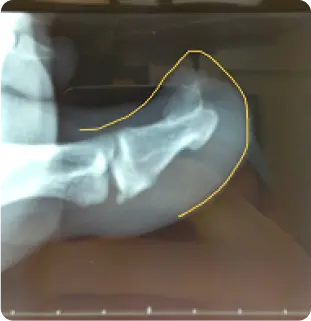

Some podiatrists and GPs may treat it as an ingrown toe nail (antibiotics, nail spicule removal, PNA) but there may be no improvement. In other circumstances, some patients will notice an unusual growth beneath the toenail and pushing on that growth is usually firm and painful. In these cases I like to take an x ray of the foot to see if there is any underlying pathology – we usually see a bony growth known as an exostosis or osteochondroma which is the primary cause of the nail change/pain.

An osteochondroma is a benign (non-cancerous) bone growth that forms on the surface of a bone. Osteochondromas consist of boney growth covered with cartilage cap. When they form under the toenail, they can create unique issues due to the limited space and sensitivity of the nail bed with activity and footwear.